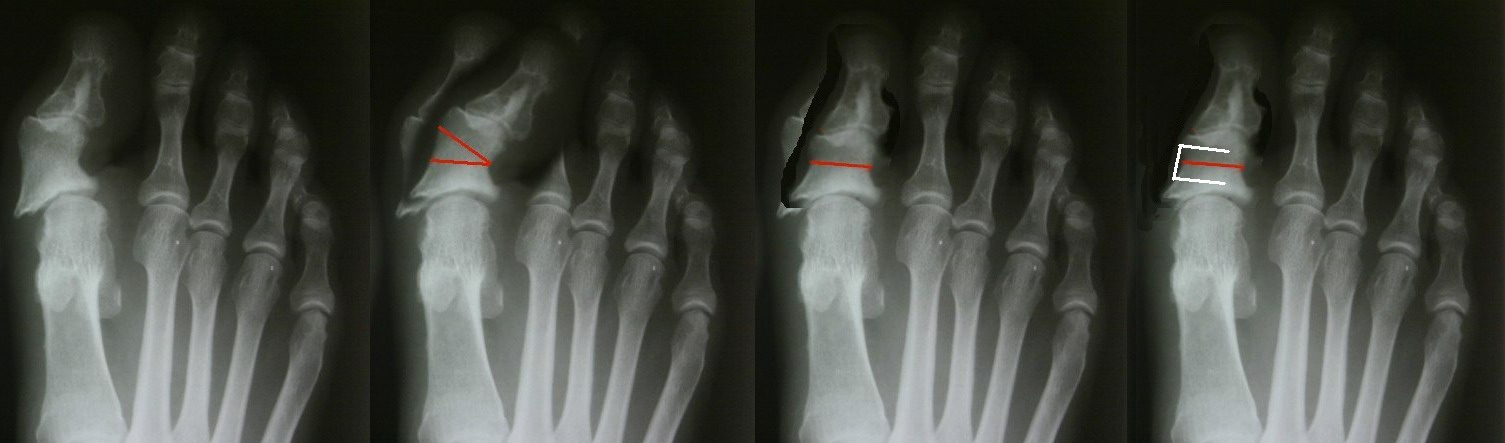

[Ortho] Неудачный результат

Имя     : St.jpg